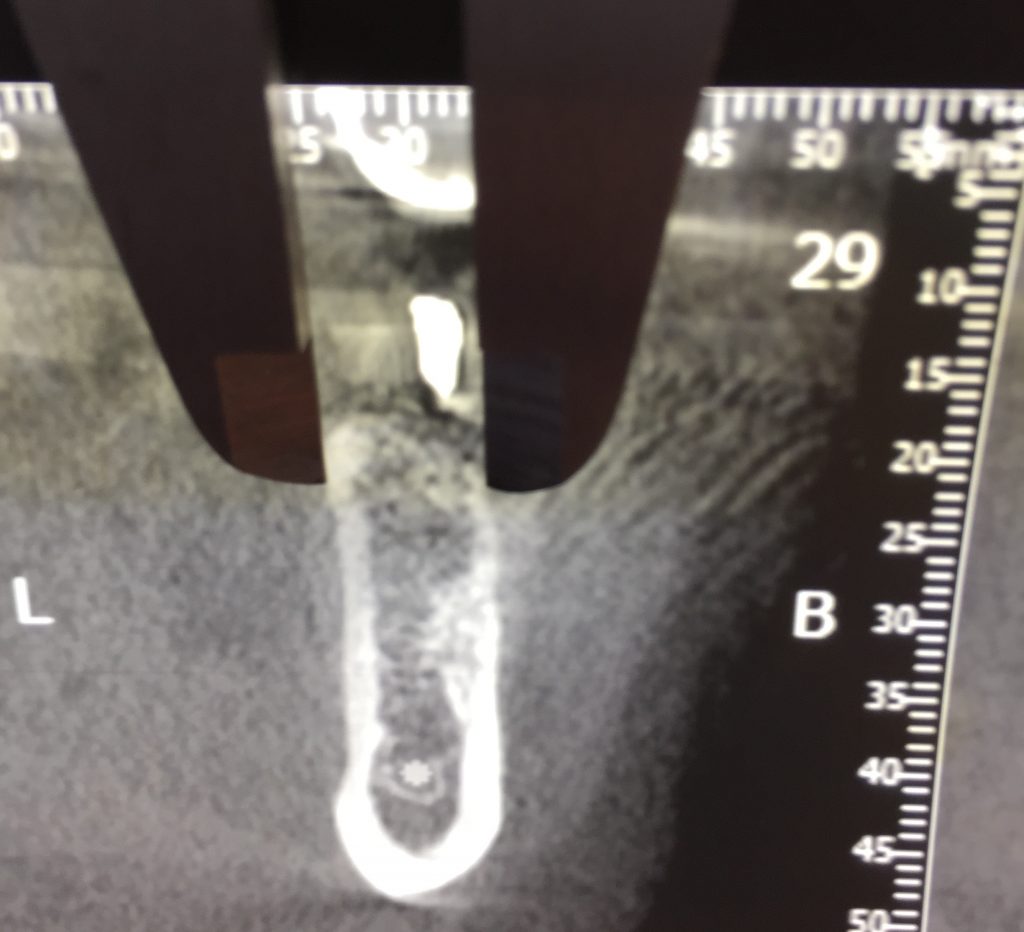

Autores: PRÓLOGO Asimismo, desde el punto de vista pedagógico, el profesional nobel en la materia tiene a su alcance la posibilidad de corregir cualquier posición implantaría en el ordenador, planear los provisionales y plasmarlos en la bio réplica antes de tocar al paciente a operar. Todos estos razonamientos nos llevan a presentar un caso de condiciones muy favorables para poner en práctica estos métodos como primer acercamiento a una Odontología Digital de alta calidad, con medios informáticos, que ya están presentes en la profesión de hoy en día, y será la protagonista única del futuro. Por otro lado, después de numerosos estudios que nos llevan a plantear el “gap” entre implante y pilar(abuttment), como principal responsable de la periimplantitis dado que la microbiota presente en el mismo es imposible de limpiar y en su presencia la cortical ósea reacciona reabsorbiéndose, nos ha llevado a utilizar implantes monobloc ya que los ejes implantarios y protéticos coincidían, y nos permitían su uso. Además, el circonio, ha mostrado a la luz de estudios muy recientes, una preservación y adhesión de los tejidos blandos superiores al titanio, tanto en su tratamiento de superficie de la rosca como a nivel gingival. DESARROLLO Paciente varón de 68 años, con antecedentes de radio/quimioterapia cinco años antes, con Rehabilitación Oral de los cuatro cuadrantes, con una Oclusión Mutuamente Compartida conservada, (REF.8) la que fracasa en el cuadrante 4, 19 años después. El mismo presentaba un puente de porcelana sobre circonio con pilares en 44 y 47, reemplazando el edentulismo de 45 y 46. Se produce la fractura del PM del 44, y ante una endodoncia antigua y corta, se decide implantar las zonas edéntulas, conservando temporariamente los pilares, hasta producida la oseointegración, para entonces también exodonciar el 44. DIAGNÓSTICO Tomamos impresiones del maxilar antagonista, Arco Facial Estático y realizamos montaje del mismo mediante la sistemática ARTEX. Producimos la relajación del músculo Pterigoideo Externo, para obtener la ORC (Oclusión en Relación Céntrica) mediante el método de Laminillas de Long, basado en el concepto de INERVACIÓN RECÍPROCA. Esto nos permitirá montar el maxilar inferior, tanto en su forma de: La primera para practicar la cirugía guiada y comprobar su eficacia, y el modelo de yeso para ser escaneado y confeccionar la GUÍA QUIRÚRGICA. La Biorréplica la obtenemos transformando los archivos DICOM que nos da el CBCT en archivos STL, y a partir de ellos, mediante una tecnología de PROTOTIPADO RÁPIDO, la obtención de un objeto físico en 3D a través de la aglutinación selectiva de una sucesión de capas de polvo. Procedemos a montar la biorrèplica y el modelo de yeso del caso. Podemos verificar la exactitud de las medidas del hueso residual en la bio réplica y compararlas con el scanner. Arrojando un resultado de 8,5 mm de cortical externa a cortical externa. Pudiendo también medir la distancia hasta el dentario. y comparar gracias a la ventana lateral de la biorréplica Dándonos 22mm de distancia. Con lo cual deducimos que implantes de 4,1mm por 12 mm serán perfectamente rodeados de hueso. Medimos también la distancia desde oclusal del antagonista, hasta el hueso desnudo. Lo mismo que, mediante la utilización de la guía radiológica, con un material radiolúcido colocado en gingival de la misma, podemos medir la altura de la encía. Con lo cual podemos calcular la altura del pilar. Es entonces cuando con el programa COC Diagnostix se realiza la programación final: Obteniendo no solo la ubicación, largo, ancho y ángulo de los implantes sino también los provisionales mediante CAD CAM. Ya entonces podemos hacer la práctica quirúrgica en la bio réplica, mediante la guía quirúrgica, instalando los implantes de prueba que no serán los de circonio, ya que la casa no cuenta con ellos, pero si otros de las mismas dimensiones. TRATAMIENTO Entramos ya en la cirugía propiamente dicha. Antisepsia de la zona a operar y zonas anexas. Comprobación del perfecto ajuste e inmovilidad de la G.Q. en boca durante la cirugía. Marcado de la encía y perforación de la cortical. Visión a través de la Guía de la mínima intervención anterior. Comprobación sin Guía. Incisión mínima mesio distal, para apartar y conservar encía queratinizada. Secuencia de drills, perforando a profundidad requerida Observación del Mínimo Trauma Implantes Strauman de Zirconio Monoblock en blíster y montádo en contrángulo reductor. Instalación controlando torque con contrángulo reductor. Comprobación clínica. Comprobación Radiográfica y con Guía. Toma de impresiones, y armado de modelos con técnicas de pasividad protética. Montaje. Resultado de las provisionales ejecutadas por CAD CAM Al no estar conformes con el resultado decidimos desechar dichas provisorias y optar por repetirlas. Nuevas provisorias realizadas mediante encerado convencional. Estado de los tejidos blandos. Provisorias en boca. Oclusión de Estímulo Inmediato. Ref.10: Carga inmediata .Alberto y Diego Bechelli. Comprobación mediante CBCT post operatorio Componentes del equipo (En la próxima presentación, mostraremos las coronas definitivas de porcelana sobre circonio, y la desoclusión provocada por una OCLUSIÓN MUTUAMENTE COMPARTIDA, sobre estos implantes y otros seis mas) REFERENCIAS

Realizamos previamente una Rx periapical Dígora (radiovisiografía) y un CBCT (TAC de haz de cono) con férula radiológica, marcando ambas raíces del 46 y la raíz del 45.

FIG: 5-6-7-8

FIG: 9-10-11-12